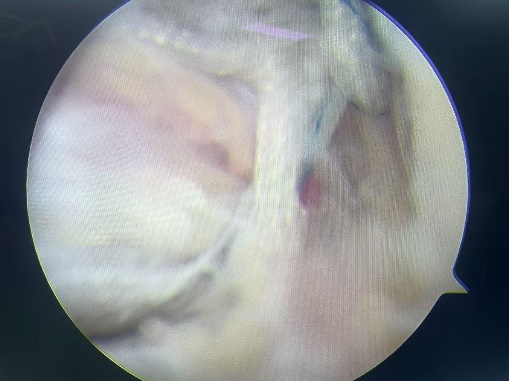

术中锚钉置入情况

术中修补韧带后情况